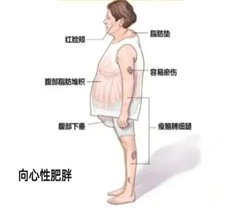

②分泌皮质醇的腺瘤:可能引起“库欣综合征”,表现为向心性肥胖(肚子大、四肢瘦)、满月脸(脸变圆)、背变厚(水牛背),痤疮、皮肤紫纹,还可能伴随血糖升高、骨质疏松。